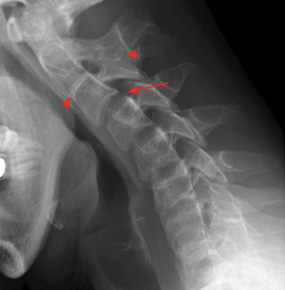

A 72-year-old female patient arrived at the Emergency Department (ED) of the Hospital of Lithuanian University of Health Sciences Kaunas Clinics. The patient presented with complaints of speech disturbances, neck pain, numbness in her hands, and difficulty climbing stairs. The symptoms had persisted for over two days without improvement. Based on her medical history, in April 2023, the patient had been treated for a severe episode of neck pain, and a neck X-ray was performed, revealing congenital partial fusion of the C2–C3 vertebrae, as indicated by arrows in Figure 1.